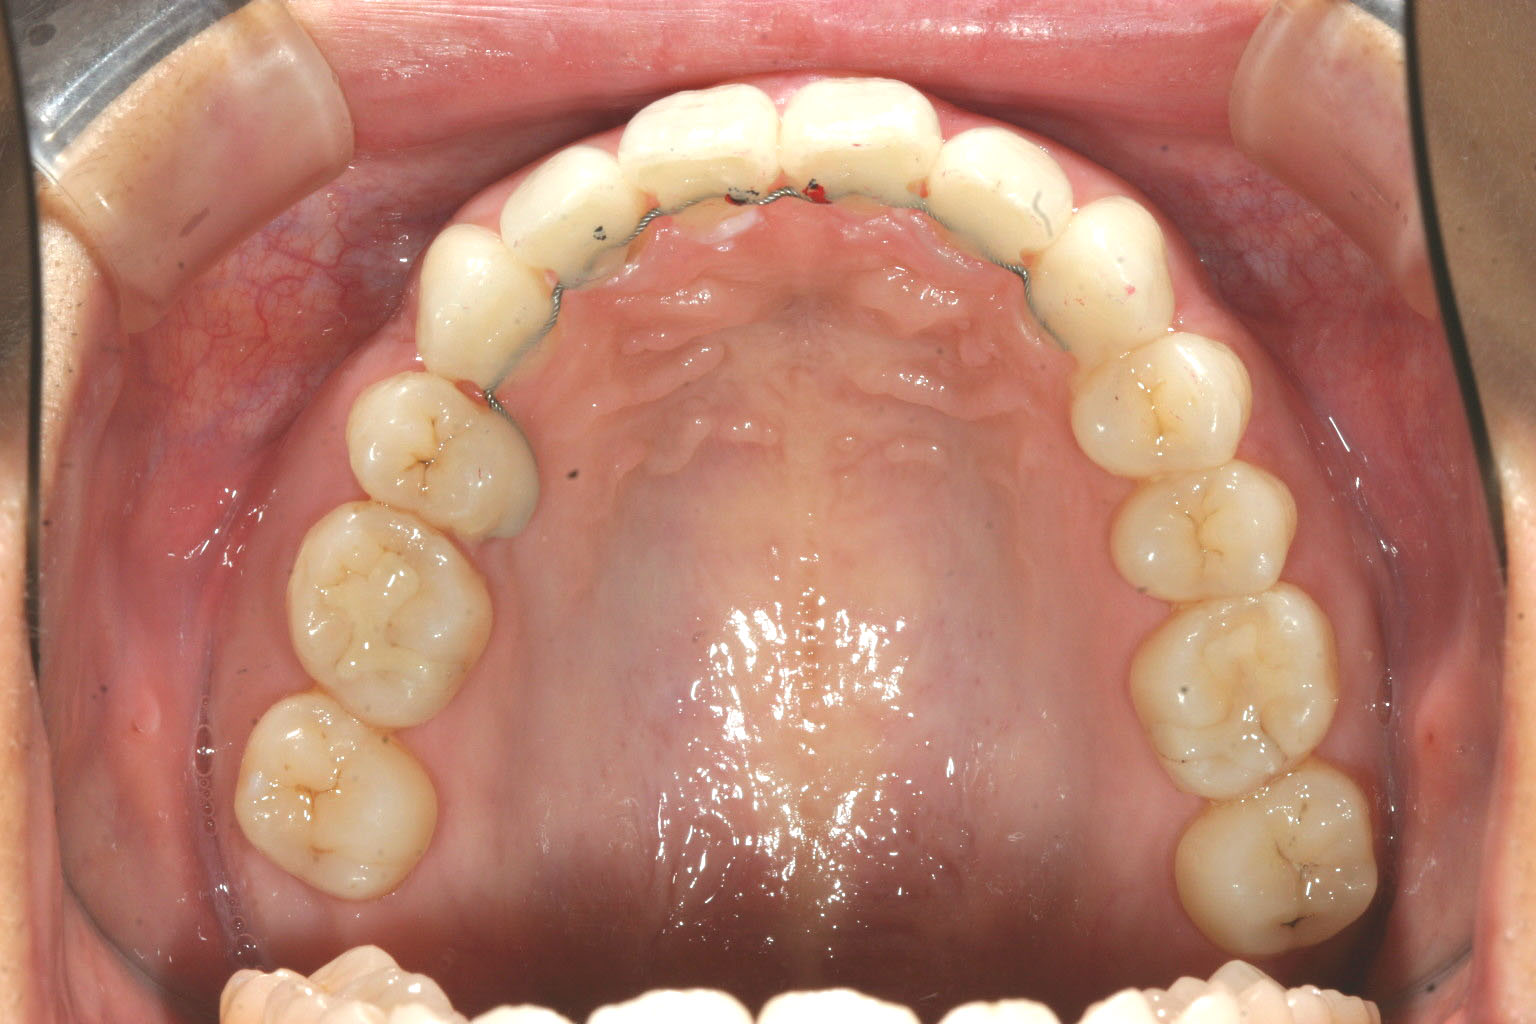

前歯が少し翼状捻転してます。

前歯に自家製バイトアップジグが入ってアップダウンエラスティック使用してます。

右側第一小臼歯のみ抜歯し翼状捻転も綺麗に改善してます。